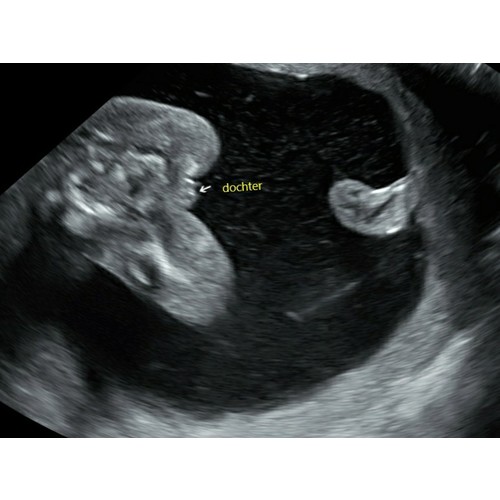

Zelf niet meegemaakt. Met 14 weken via nipt test zeiden ze jongetje, dan 16 weken heeft de gyno het bevestigt en piemeltje laten zien, en nu 24 weken bijna, normaal nog steeds hetzelfde..

Hier werd deze zwangerschap met 17 weken ook geroepen 1 meisje en 1 durf ik niet te garanderen maar denk ook een meisje.

No way dat ik iets durfde te kopen deze keer.. Inmiddels 4 echo's verder en nog steeds 2 meiden. Dus nu zijn we wel gaan shoppen op roze! Maar ik wilde het eerst een paar keer horen van ze 😅